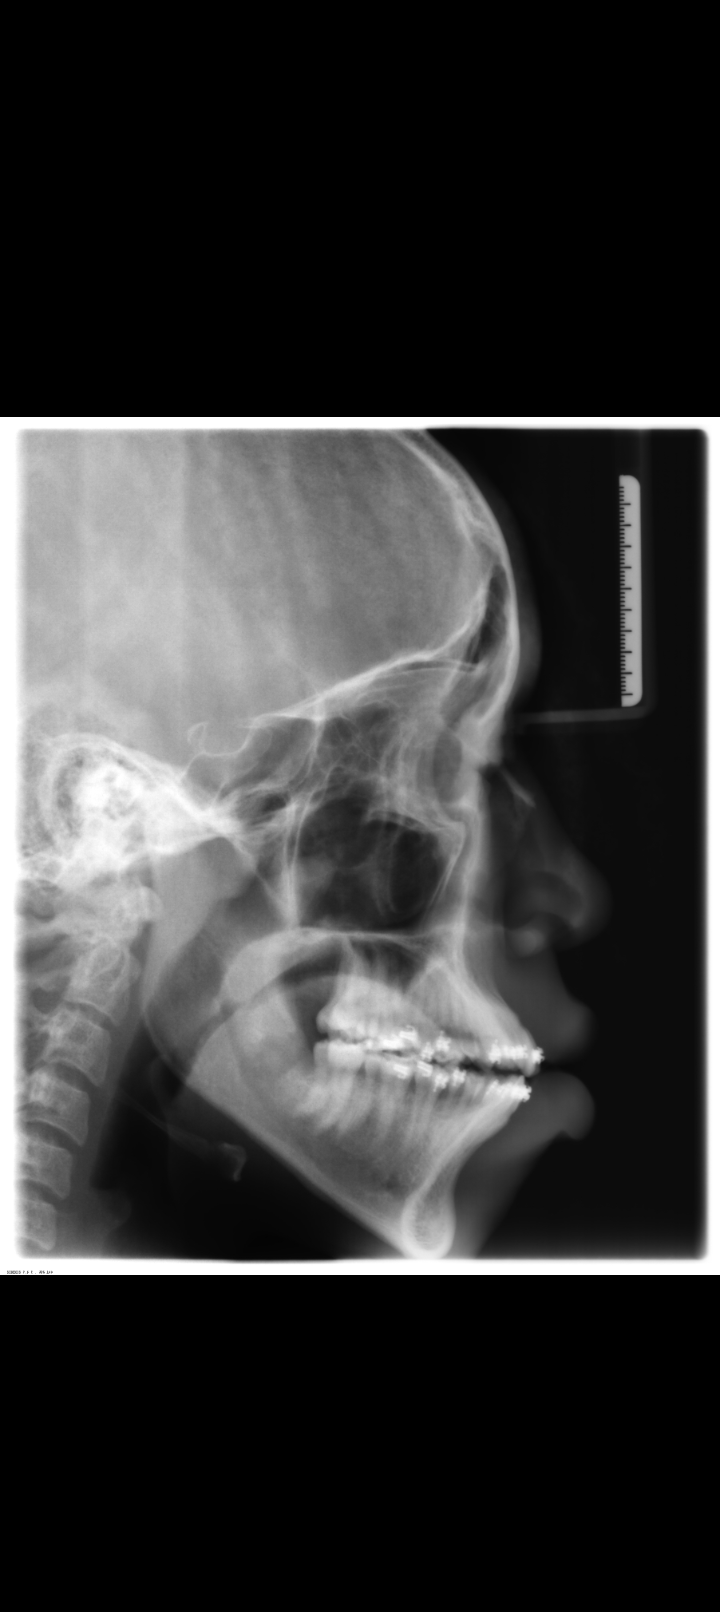

Ortho already removed 4 wisdom teeth

Now wants to remove 4 premolars

To fix my crooked teeth and bimaxillary protrusion

What should I do to fix my teeth without removing more teeth? Wtf